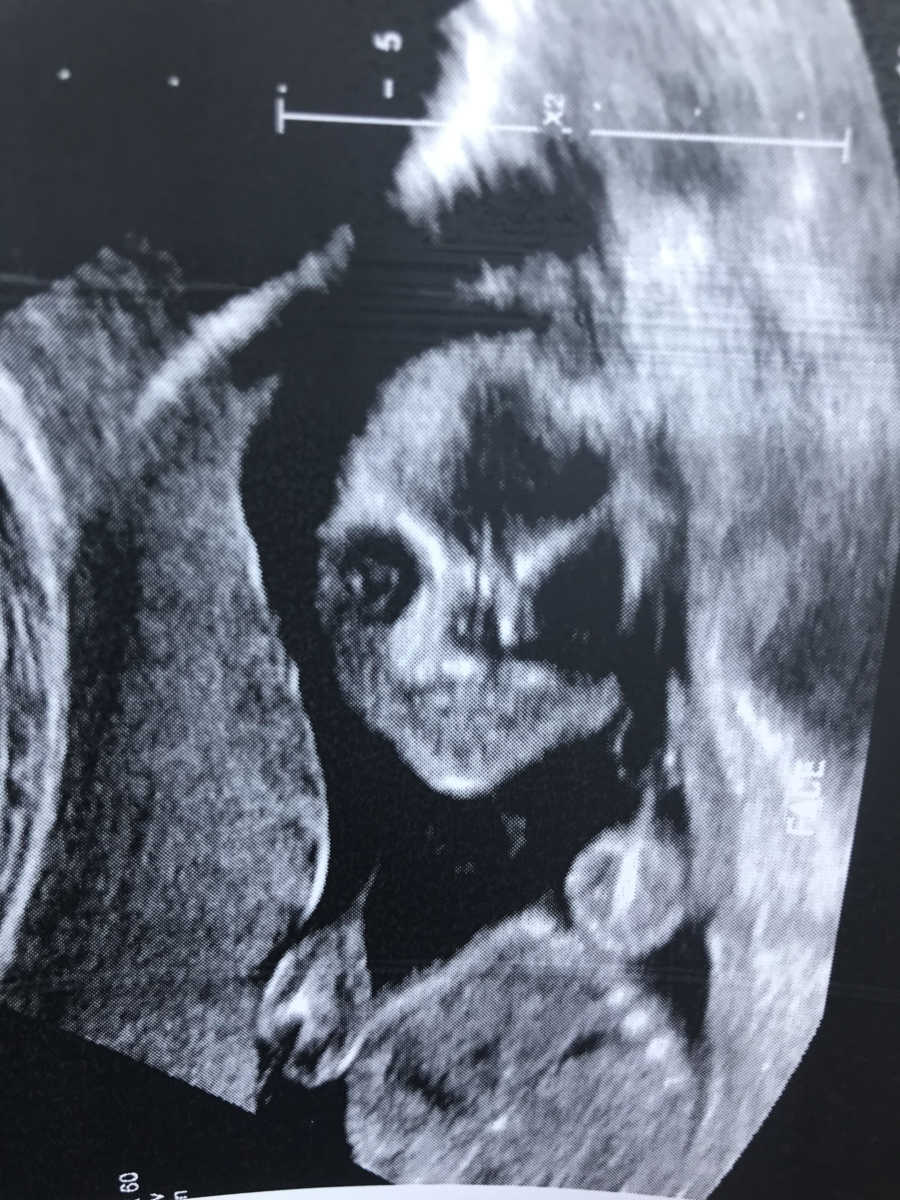

Durante o exame, a técnica foi amigável e gentil, mas assustadoramente silenciosa. Eu simplesmente sabia que, no fundo, algo não parecia certo. Após a consulta, sentei-me no carro com um envelope de fotos na mão e disse a Lyndon que me sentia inquieta. Ele me garantiu que provavelmente tudo estava bem. Procurando conforto, tirei minhas cobiçadas fotos de ultrassom do grande envelope laranja que o técnico havia me dado. Se eu não estivesse sentada, poderia ter caído. ‘Nosso bebê parece uma máscara de Halloween!’ Eu gritei. Três imagens de aparência assustadora me encararam.

Vistas frontais do rosto do meu bebê precioso (ou seja, esqueleto). Até meu marido calmo, tranquilo e controlado parecia um pouco pasmo. ‘Por que eles nos dariam estes ?!’ Eu questionei várias vezes. Claramente, algo estava errado, ou eles teriam pensado em nos imprimir algumas fotos típicas de ‘mídia social’ do meu feto. Respondendo ao meu questionamento incessante, Lyndon repetidamente me garantiu que nosso feto era fofo e, mais importante, ele realmente acreditava que nosso bebê estava bem. Eu não consegui me acalmar. Nos novos dias, tive a mesma conversa com quem quisesse ouvir. Tentei fazer piadas sobre meus medos, mas meus pensamentos continuaram a ser alimentados pela ansiedade.